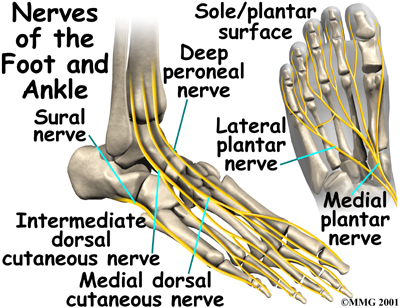

Nerves

The nerve supply of the ankle is from nerves that pass by the ankle on their way into the foot. The

runs behind the medial malleolus. Another nerve crosses in front of the ankle on its way to top of the foot. There is also a nerve that passes along the outer edge of the ankle. The nerves on the of the ankle control the muscles in this area, and they give sensation to the top and outside edge of the foot.